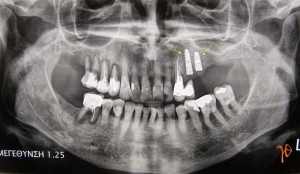

Η ασθενής, πριν την έναρξη της θεραπείας με Prolia, είχε υποβληθεί με επιτυχία σε τοποθέτηση οδοντικών εμφυτευμάτων στην άνω γνάθο, αριστερά(Εικόνα 1). Δεν είχε λάβει την δεύτερη δόση και 10 μήνες μετά την λήψη της πρώτης δόσης είχε υποβληθεί σε δύο εξαγωγές(#46, #37) χωρίς να εμφανίσει επιπλοκές.